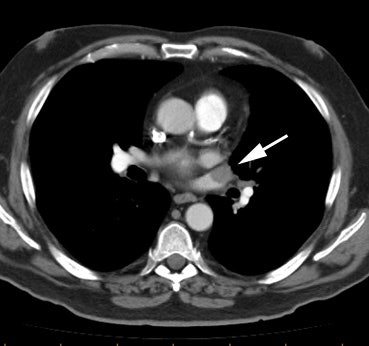

Example 2: This patient with non-small cell lung cancer demonstrates many findings which are suspicious for mediastinal invasion. There is greater than 3 cm of contact between the mass and the mediastinum, loss of the mediastinal fat plane between the mass and the left pulmonary artery, deformity of the left pulmonary artery, and pericardial thickening (yellow arrows). The patient also demonstrates contralateral mediastinal adenopathy (N3 nodes -- white arrow), subcarinal adenopathy (SC), and bilateral pleural effusions.